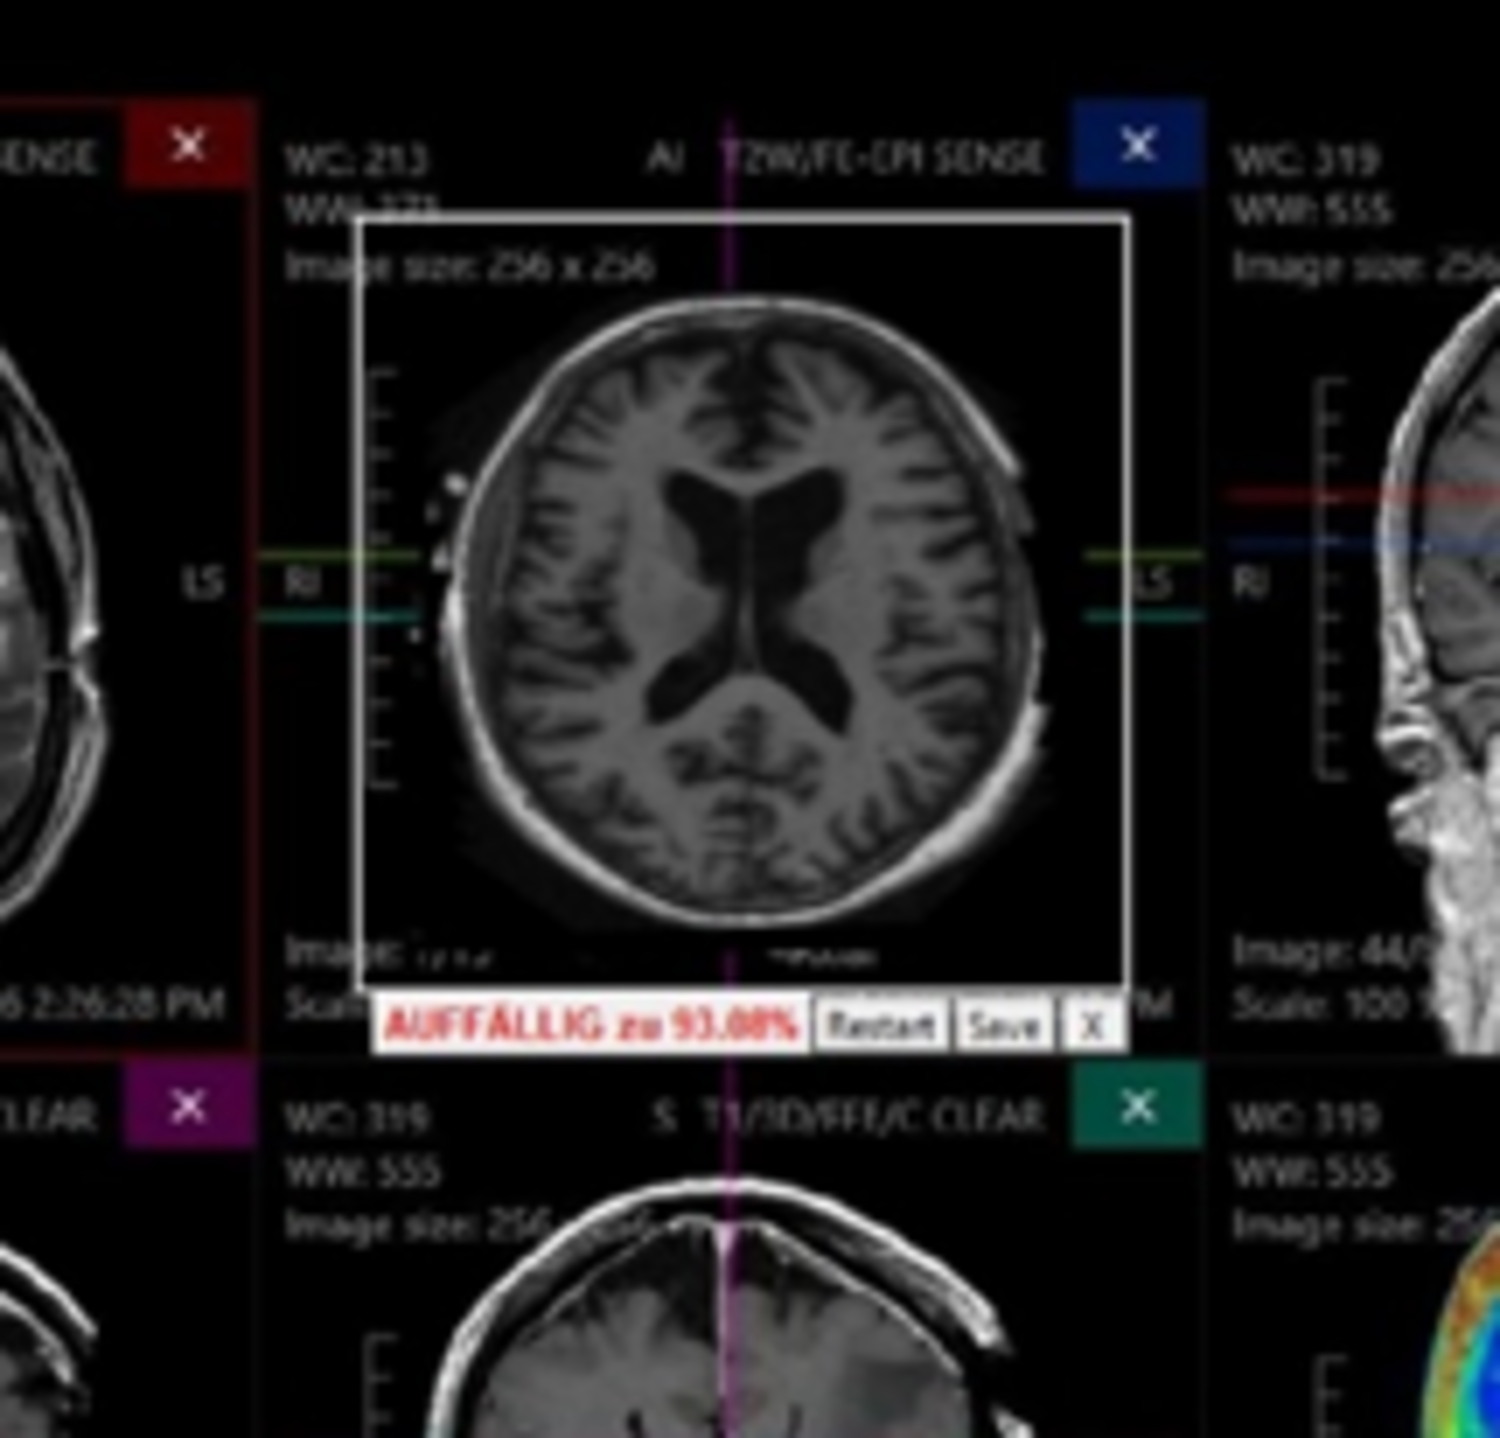

Machine learning methods, in particular using deep neural networks, are celebrating ever new successes in the analysis and classification of medical images. It is clear that in many applications, the algorithms are already achieving at least human-like decision-making accuracy. However, it is still unclear how networks trained on a specific data situation will behave in a different data situation. For example, when imaging hardware or imaging parameters differ from radiology to radiology.

In the BMWi-funded ZIM project NeuroTEST, the Medical Technology research group (project lead Prof Remmele) is developing methods for the systematic validation of neural networks (use case: segmentation of MS lesions) together with the Munich start-up deepc. To this end, methods of statistical experimental design are being researched, whereby AI algorithms are systematically tested on data from different recording protocols. The project at HAW focuses on the simulation and synthesis of this data in order to be able to provide arbitrary data domains for the stress tests.